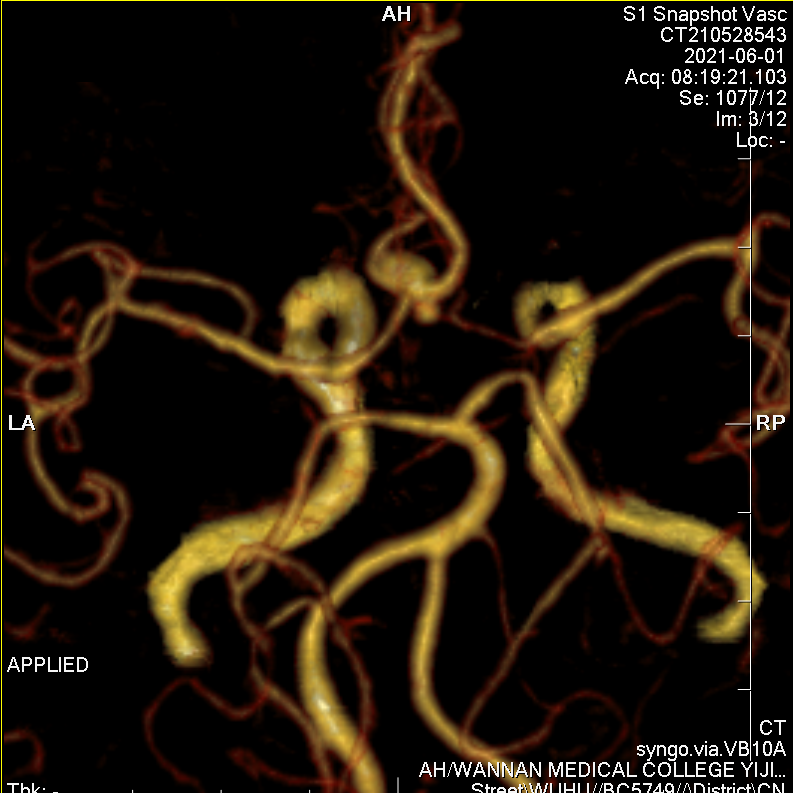

头颅CTA提示左侧优势供血前交通动脉动脉瘤。

牛角弓、颈动脉极度迂曲。

瘤颈与载瘤血管关系不甚清楚,故行压颈3D造影。